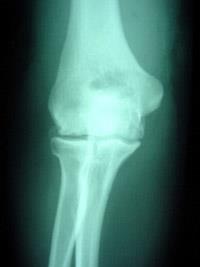

osteoarthritis of the elbow

X-ray showing an elbow with early degenerative changes.

Elbow osteoarthritis that occurs without previous injury is more common in men than women. Onset typically occurs in people 40 to 50 years of age or older, but some patients will experience symptoms earlier.